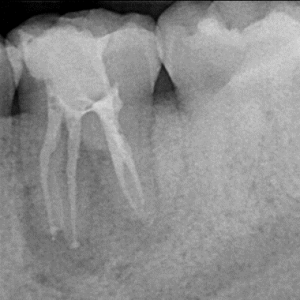

Root Canal / Retreatment

Clinical Cases